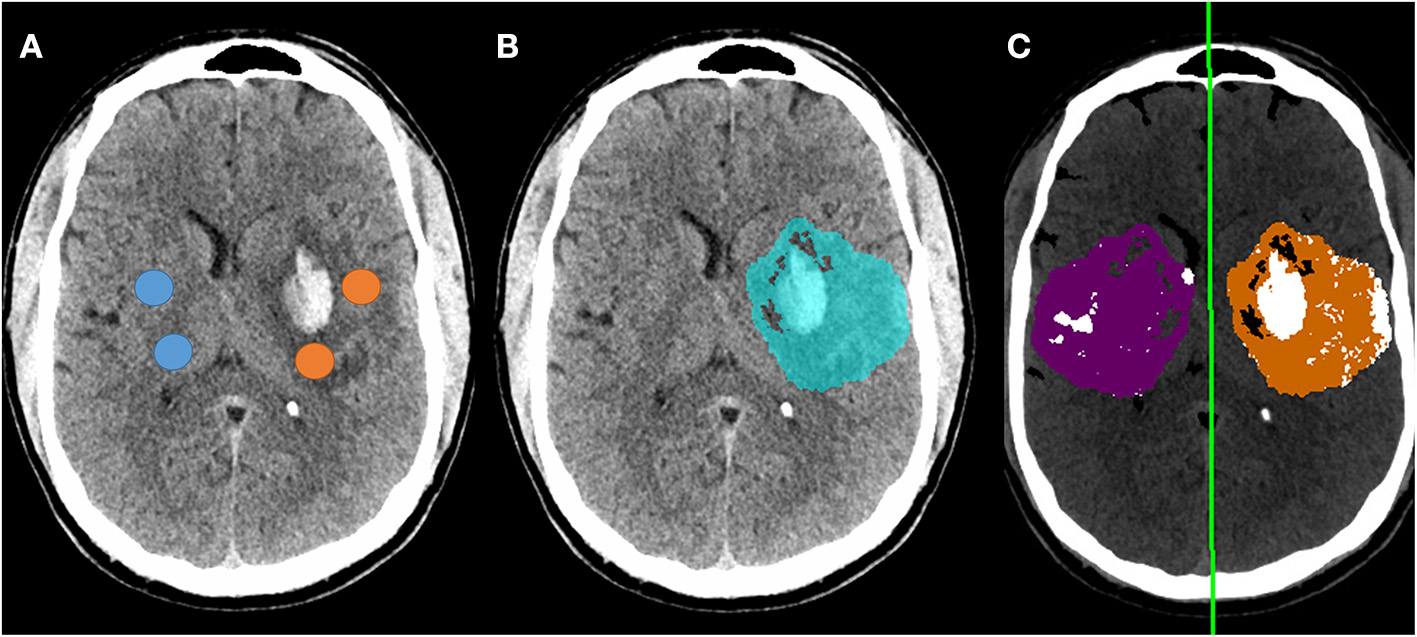

NWU was manually estimated on these 66 scans by two raters, using the ASPECTS ROI-based approach, with strong intraclass correlation between raters (ρ = 0.88, p = 3 × 10−54). Fully automated NWU was obtained by applying the automated infarct segmentation in 63 cases (two excluded for failure of infarct segmentation, one due to lack of voxel information in file header). The automated NWU (median 24.6, IQR 19.8–26.9) exhibited excellent agreement with NWU obtained from the manually drawn infarct masks (ρ = 0.98, Supplementary Figure 9). These values also correlated well with the manual ROI-based method (ρ = 0.68, Figure 3C). There was minimal bias (mean difference of 2.7) in NWU measurement, with no greater discrepancy in those with increasing severities of hemorrhagic transformation (Figure 3D). For example, in one case with focal hematoma, the manual NWU was 21.0 and the automated value was 21.6 (Figure 4).

Figure 4

Example of follow-up CT in a patient who developed a focal parenchymal hematoma within the region of infarction. (A) Original non-contrast CT with regions-of-interest manually placed within the infarct (avoiding hemorrhage) and in contralateral matching regions (avoiding CSF); (B) Blue region indicates automated segmentation of infarct lesion; (C) Processing of follow-up CT to measure NWU using automated infarct mask, with removal of voxels representing CSF (white regions within purple normal mask) and voxels outside the range of 0-40 HU (removing most regions of hemorrhage). The manual NWU was 21.0 and the fully automated NWU was 21.6.